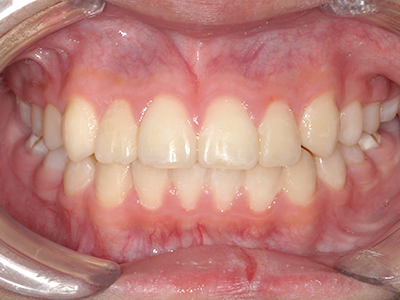

歯並びやかみ合わせを正しく整えると、笑顔や発音の自信につながり、むし歯・歯周病・口臭の予防にも役立ちます。

矯正装置を装着し、調整しながら少しずつ歯を移動させ、歯並びを整えていきます。